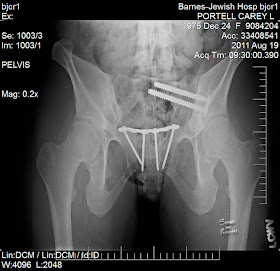

During my first check up with my surgeon, Greg reminded me about the most important complaint I'd had. How could I have forgotten? Relaying to my surgeon that my pubic bone had been "popping" for the last week was imperative. It gave a pretty big wallop, one that Greg could hear and if he was carrying me, he could feel. My surgeon stopped walking and talking instantly. I did not enjoy the look on his face. After a few questions, he immediately scheduled me for some x-rays and a CT of my pelvis. He dropped the bomb on us that my pelvic fracture did not heal as expected. The surgeon must put two bolts in my left posterior pelvis and a plate and screws on my pubic bone to hold my pelvis together. Had I known, how many more surgeries I would have to recover from, I probably would not have taken this unplanned surgery so hard.

Two bolts and four very long screws were installed that day. Yes, we estimated maybe they were a little too long in length for my anatomy. Six months later the plate and screws were removed, only to allow my pubic bone to start popping again. This meant that one side of my pubic bone was overlapping the other and when I moved, it popped or scraped against each other to return to it's original position. Not great. Four months later a plate and six screws were reinstalled and this is how I will always stay.